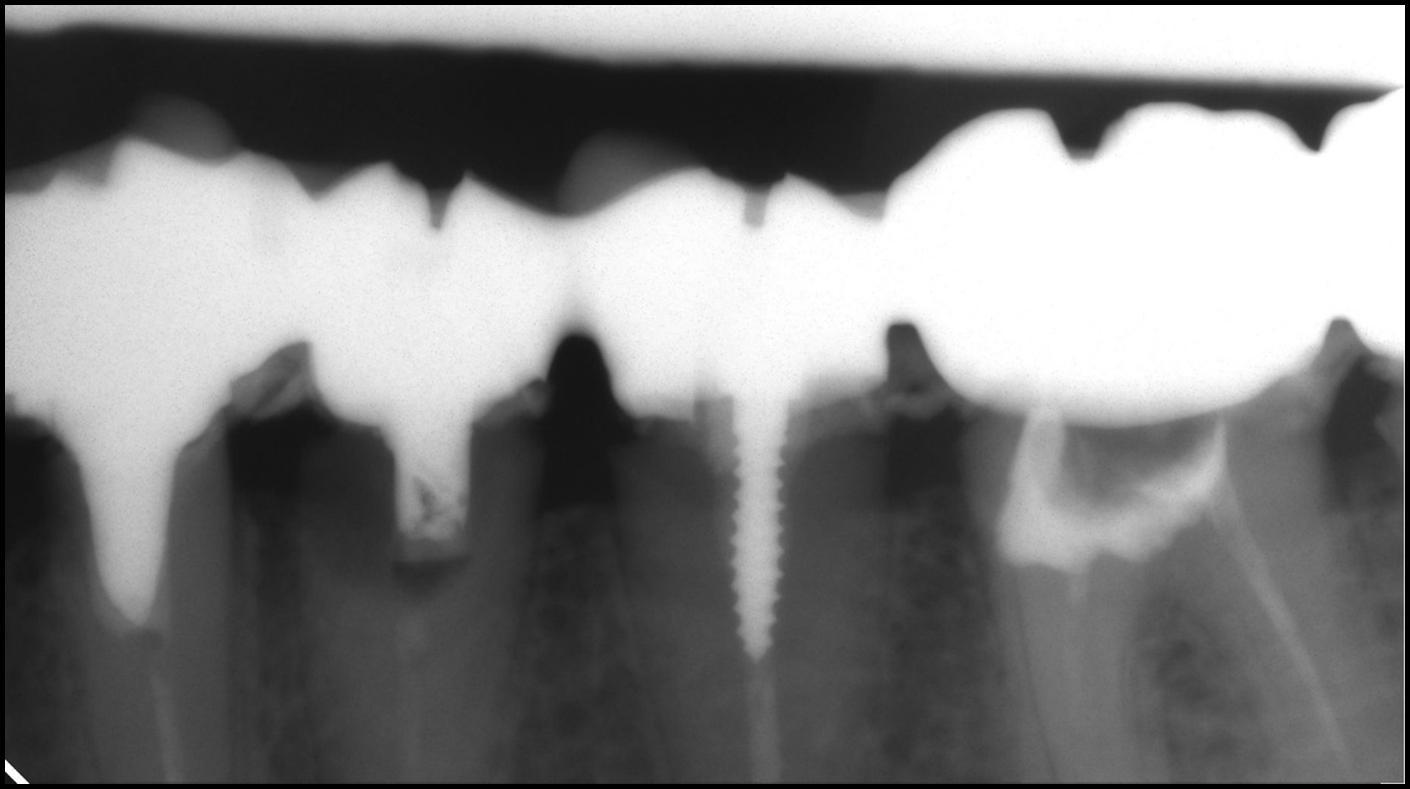

Проходження непрохідних каналів

• клініка

• діагностика

• менеджмент

Чи бувають непрохідні канали? Які ознаки прохідності? коли треба зупинитися і ухвалити рішення не йти далі. Механізм роботи зі ступенями із застосуванням мікроскопа і без, Механізм нівелювання сходинок. Фішки обтурації каналів при неможливості обійти або нівелювати сходинки.